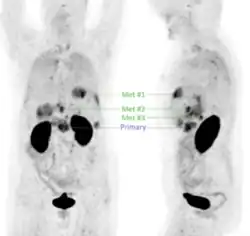

In a cohort of 20 suspected (19 confirmed) head-and-neck squamous cell carcinoma (HNSCC) cases, 68Ga-Trivehexin PET had a higher sensitivity (92.5%), positive predictive value (PPV, 100%), and accuracy (93%) than the standard 18F-FDG PET, for which sensitivity, PPV, and accuracy were 90%, 93.1%, and 84.3%, respectively.[32] 68Ga-Trivehexin was furthermore applied in a case of tonsillar carcinoma metastasized to the brain (see image).[31]

- ^ a b c Rehm J, Winzer R, Notni J, Hempel S, Distler M, Folprecht G, et al. (September 2024). "Concomitant metastatic head-and-neck cancer and pancreatic cancer assessed by αvβ6-integrin PET/CT using 68Ga-Trivehexin: incidental detection of a brain metastasis". European Journal of Nuclear Medicine and Molecular Imaging. 51 (11): 3469–3471. doi:10.1007/s00259-024-06750-6. PMC 11368998. PMID 38771514.